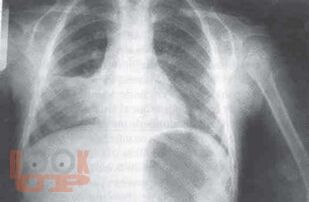

В данном томе многотомного руководства по детским болезням рассмотрены актуальные вопросы пульмонологии, систематизированные в виде современных представлений о заболевании органов дыхания. Приведены новейшие теоретические и клинические данные по анатомо-функциональной характеристике, этиологии, патогенезу, эпидемиологии, патоморфологии, патофизиологии, классификации заболеваний. Представлены методы диагностики и дифференциальной диагностики в детской пульмонологии. Даны практические рекомендации по лечению отдельных форм пульмонологических заболеваний и проведения реабилитационных мероприятий. Руководство иллюстрировано фотокопиями рентгенограмм, томограмм и др.